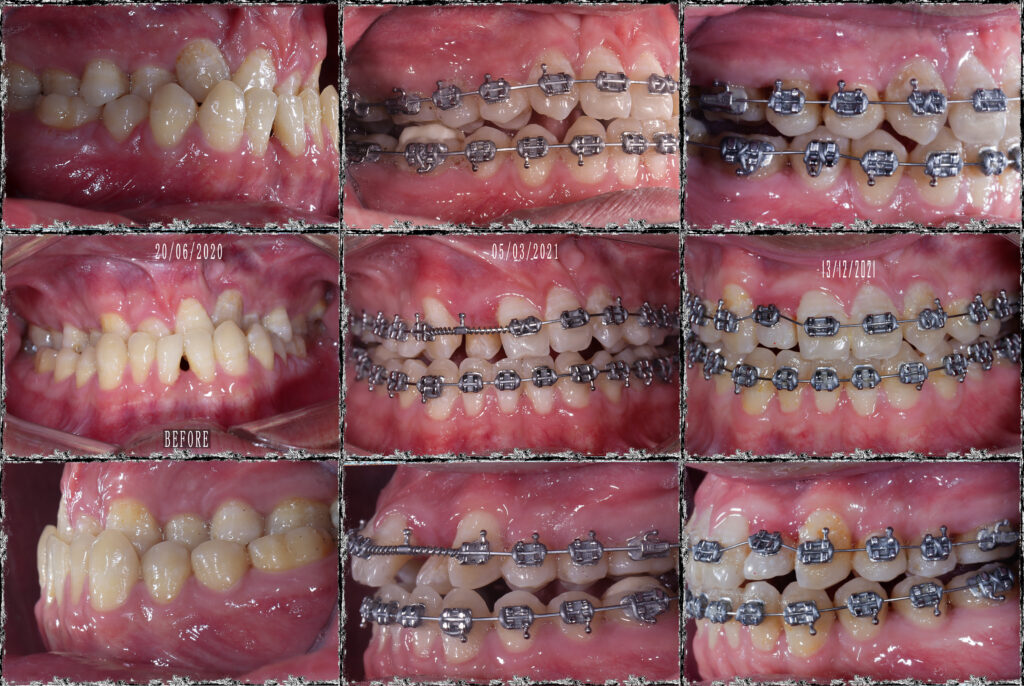

BN khớp cắn hạng 3, hàm trên nằm trọn trong hàm dưới. Hàm trên cực hẹp. Chỉ định nong hàm với ốc nong nhanh và dây Damon. Dựng trục răng 7 hàm dưới, torque lại trục răng hàm trên, giải “hẹp” hàm trên, kéo răng lệch phía khẩu cái ra ngoài. Giải khớp cắn ngược răng cửa, cắn kéo R7, tất cả dùng dây cung thẳng liên tục.